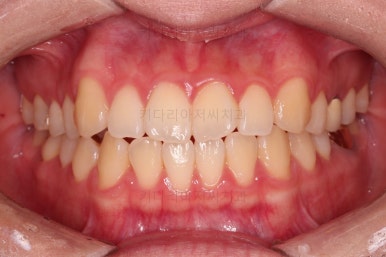

1. 처음 내원 시의 입안의 모습

부산치아교정잘하는곳 키다리아저씨치과에 처음 내원하셨을 당시의 입안 모습입니다.

얼핏 보면 많이 삐뚤어지지는 않은 편인데, 눈에 바로 띄는 앞니가 뻗쳐 있으면서 획 돌아있는데요. 정렬이 필요한 상황이었습니다.

어금니쪽은 많이 삐뚠 편은 아니었으며, 윗니 앞니가 많이 앞으로 뻗쳐 있는 상태였습니다.